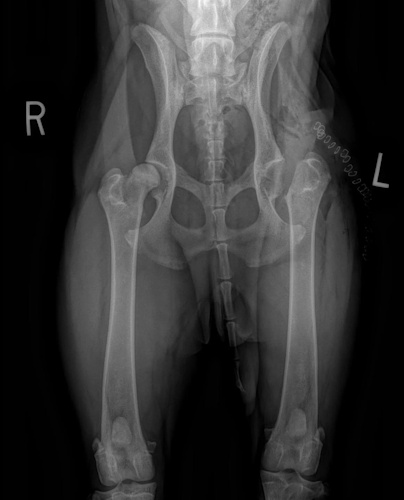

Hip Dysplasia

Hip Dysplasia in canines

Surgical Treatments of Hip Dysplasia

- Juvenile Pubic Symphysiodesis (JPS)

- Triple Pelvic Osteotomy (TPO)

- Total Hip Replacement (THR)

- Femoral Head and Neck Excision (FHNE)